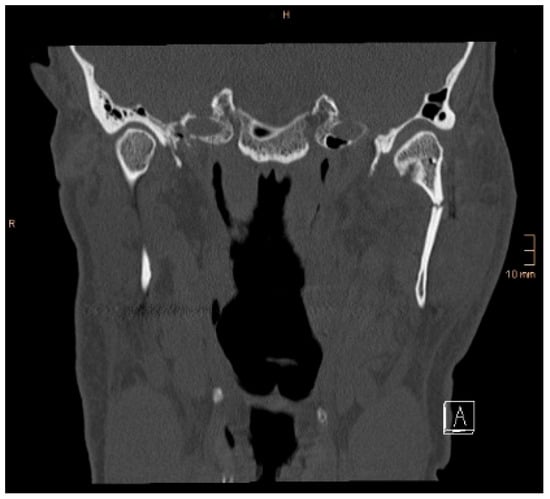

Figure 5. Coronal CT scan showing both condyles after ORIF. A widening of the mandible, caused by a small lingual gap that persisted even after lag screw osteosynthesis at the symphysis, resulted in an angulation of the condylar neck on the right-hand side (same patient as in Figure 3 and Figure 4). The image shown was taken on the third postoperative day after drainage removal and the situation did not worsen over time (last follow-up 1 year postop).

Two operations had to be redone because of inadequate reposition in the symphysis/parasymphysis with broad (>2 mm) lingual splay. In both cases, straight miniplates were removed. Osteosynthesis was achieved with lag screws. Figure 3 depicts plate osteosynthesis of a symphyseal fracture with a broad lingual gap (Figure 3). Figure 4 shows the same patient after redo operation and osteosynthesis of the same fracture with a lag-screw and a marked reduction in the lingual splaying (Figure 4). Figure 5 demonstrates the condylar reduction in the frontal plane in the same patient. Figure 6 and Figure 7 show the patient’s occlusion (Figure 5, Figure 6 and Figure 7). The third redo operation was due to nonunion and infection of an angular fracture with fracture of the two condylar plates. In this case, after removal of the infected miniplate, the angle fracture was stabilized with a reconstruction plate and a miniplate from an extraoral approach; the two broken miniplates at the condylar process were left in situ.